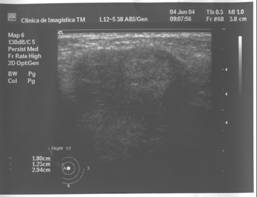

Fibroadenomul este tumora benigna cel mai frecvent asociata cu calcificari. Definitia lor histologica, corespunde unei proliferari fibro-epiteliale benigne. Exista tipuri pericanaliculare, intracanaliculare si forme mixte.